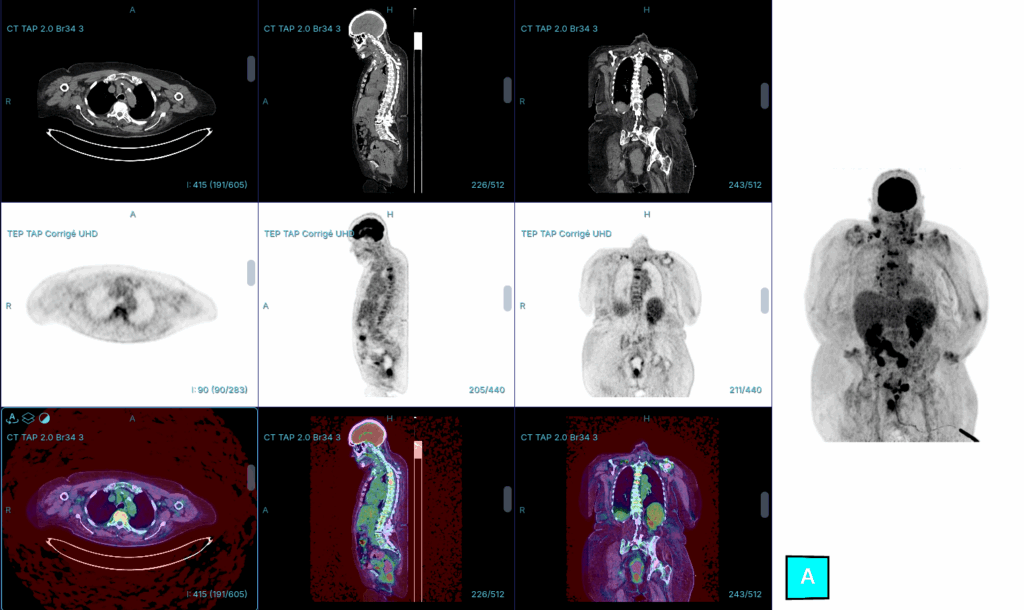

Patient suivi pour une pathologie de type X. La TEP-TDM met en évidence une fixation intense au niveau d’un épaississement pleural diffus, s’étendant de manière diffuse dans le médiastin ainsi que dans le péricarde. Une infiltration péritonéale est également présente.

Le diagnostic à évoquer est un Mésotheliome pleural , l’atteinte pleural reste assez typique.

Épaississement pleural diffus ou nodulaire avec captation intense du 18-FDG.

Effet de masse sur le poumon adjacent, parfois avec collapsus partiel.

Extension pariétale possible (muscles intercostaux, côtes, diaphragme).

Adénopathies médiastinales ou hilaires hypermétaboliques.

Le mésothéliome est une pathologie grave due à l’exposition à l’amiante. La TEP-TDM joue un rôle important puisqu’elle permet de quantifier l’activité métabolique au sein des modifications pleurales induites par cette exposition. Une fixation intense au niveau d’un épaississement pleural chez un patient en surveillance pour exposition à l’amiante doit faire suspecter une transformation maligne en mésothéliome. La TEP-TDM permet également de réaliser le bilan d’extension de la maladie et d’identifier les sites de biopsie.